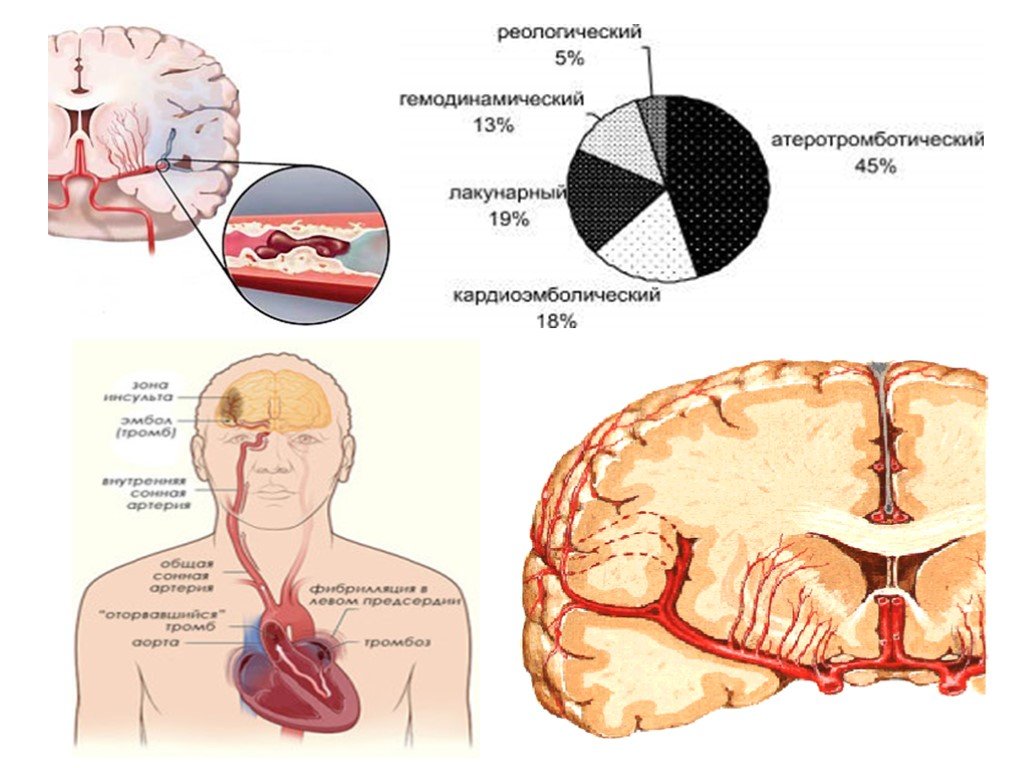

Ишемический инсульт левой стороны: симптомы и реабилитация